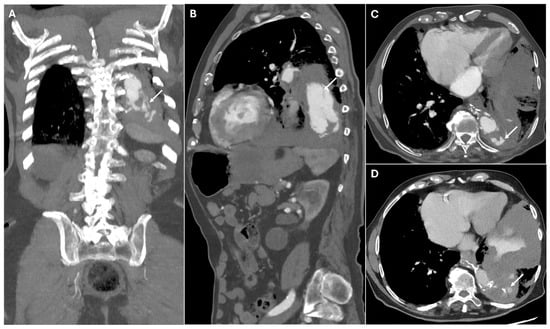

| Pseudoaneurysm | Suture failure, infection, chronic mechanical stress | Contrast-filled sac adjacent to graft, narrow neck | High rupture risk |

| Perigraft Fluid Collection and Infection | Post-surgical infection | Rim-enhancing fluid collections, intrinsic air | Can progress to graft infection and sepsis |

| Pericardial Effusion and Tamponade | Post-surgical tamponade | Fluid collection in pericardial sac, cardiac chamber compression, septal bowing | May impair cardiac function |

| Bioabsorbable Hemostatic Agents | Used for intraoperative bleeding control. | Heterogeneous masses No air–fluid levels or enhancing walls. Linear arrangement of gas bubbles helps distinguish from infection. | Mimic abscesses, hematomas, tumors or retained foreign bodies. |